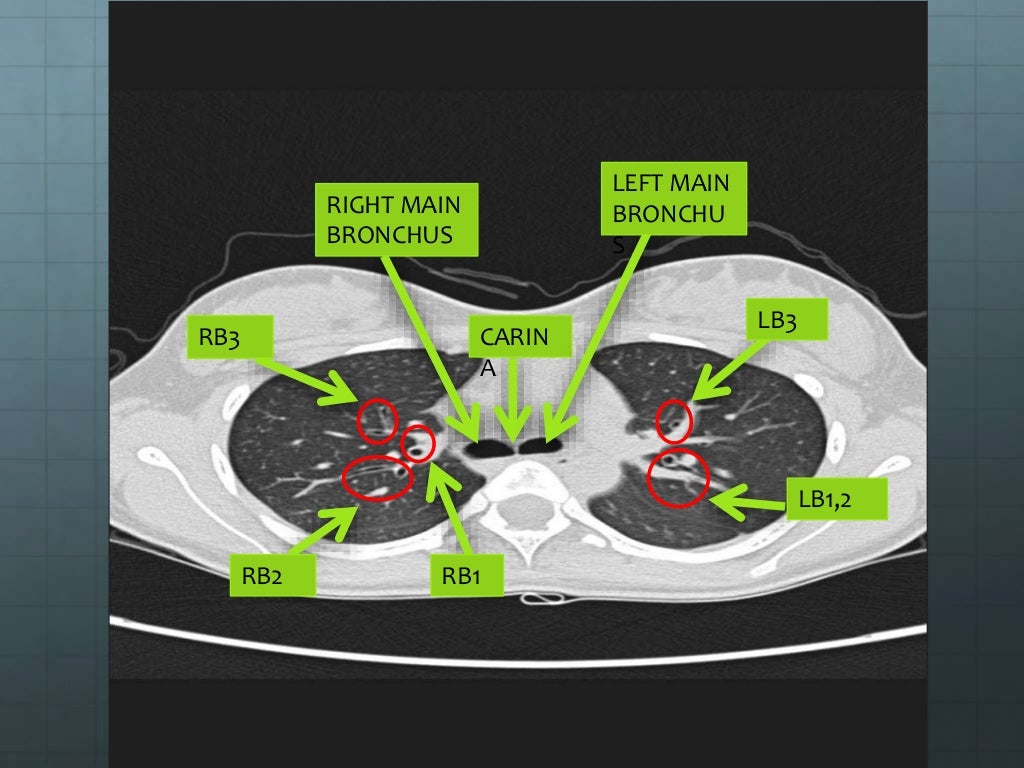

Shape Of Chest Ppt the thoracic cavity is an irregularly shaped cylinder encl osed by the musculoskeletal walls of the thorax and the diaphragm. chest shape and size • in adults thorax is oval • its anterioposterior diameter is half its transverse diameter. It consists of several components:. the thoracic cavity is an irregularly shaped cylinder encl osed by the musculoskeletal walls of the thorax and the diaphragm. They are located in the chest, either side of the mediastinum. this document provides an overview of chest anatomy and different imaging modalities used to examine the. By the end of the lecture you should be able to : the lungs are the major organs of respiration. The function of the lungs is to. • the overall shape of thorax is. the document discusses the examination of the lungs through inspection, palpation, percussion, and auscultation. Boundaries of the thorax • superior: the chest, properly called the thorax, is the superior part of the trunk located between the neck and abdomen. radiological anatomy of the chest.